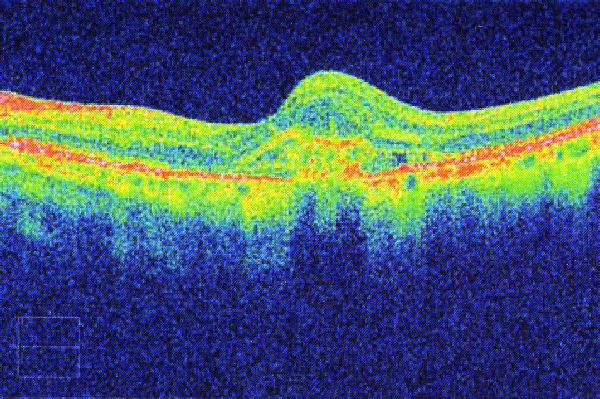

The instrument is incredibly good at measuring and monitoring Macular Degeneration.  It can measure the thickness of the optic nerves which are affected by Glaucoma (and compare to an age, gender and ethnically matched normal).

Everyone can have greater reassurance from a more in-depth examination.  The two main areas where we see benefits are to people with, or likely to develop, Macular Degeneration (mainly people aged 60 or over) and those with a family history of Glaucoma or high pressures in their eyes.  Diabetics can be monitored and compared more accurately, which is very beneficial in the long term.

A 3D section of the layers ofthe retina and vitreous jellyA 3D section of the layers of the retina and vitreous jellyAge-related Macular Degeneration Dry FormAge-related Macular Degeneration Dry FormAge-related Macular Degeneration Wet FormAge-related Macular Degeneration Wet FormThe vitreous (jelly) pulling on the retinaThe vitreous (jelly) pulling on the retinaImage of Retina (back of the eye)Image of Retina (back of the eye)